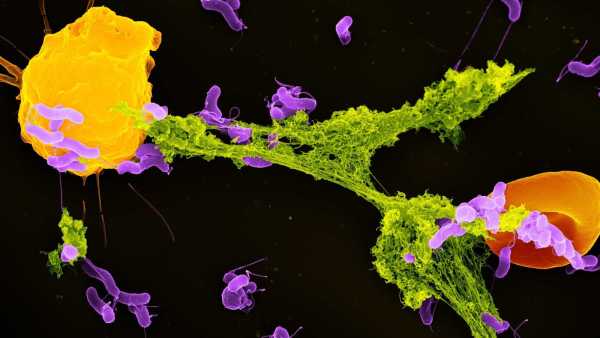

Ілюстрація, що показує пошкодження нейронів, яке може завдати розсіяний склероз. (Зображення: JUAN GAERTNER/SCIENCE PHOTO LIBRARY via Getty Images)

Відомо, що у людей з розсіяним склерозом (РС) високий рівень імунних клітин, які називаються цитотоксичними Т-клітинами, що зазвичай допомагають знищувати ракові та інфіковані мікробами клітини. Однак при РС ці клітини накопичуються в ділянках з видимим пошкодженням мієліну, але роль, яку ці клітини відіграють у цьому захворюванні, досі залишалася значною мірою загадкою.